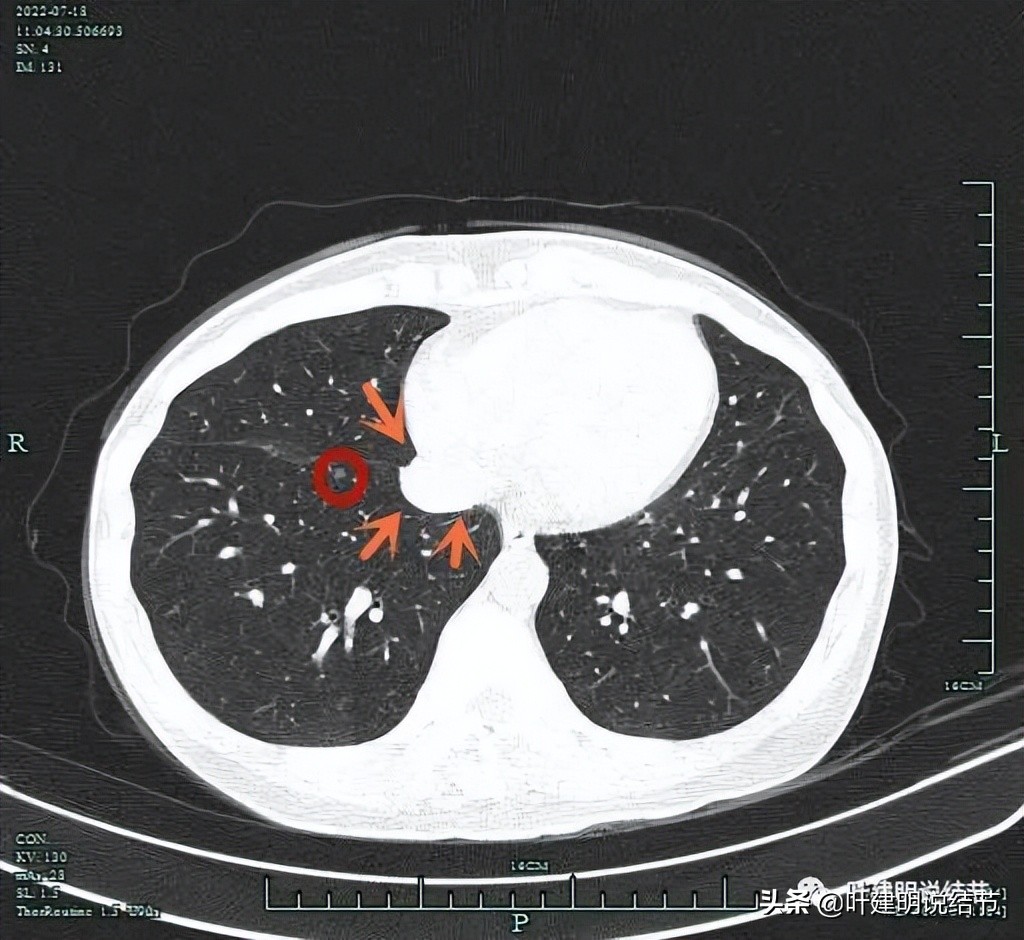

右上病灶虽然小,但密度感觉并不低,部分已经偏实性了,而且中间有小空泡征,应该要考虑恶性范围的,我判断大概率会已经是微浸润性腺癌了,至少是原位癌,但原位癌密度一般较这个要低一点。关键是位置确实挺尴尬,在右上叶邻近水平裂,与中叶交界的地方,距离肺门部大概仅约2厘米许,而且是在上叶凹进去的这个平面上,楔形切除的话,一是切割缝合器很难放到结节深面去,二是离肺门部血管近,又没有弧形的切割缝合器,容易伤到肺门部血管,许多医生可能会选择肺段切除以保证病灶能完整切除又不伤及肺门部结构。下面粉色虚线示结节到肺门血管的距离:

上图蓝色箭头示叶裂、红色示病灶轮廓与瘤肺边界清、黄色示中间有小空泡征,粉色箭头示结节与肺门部的距离仅不足2厘米,很难放置切割缝合器。

上图桔色箭头示右下肺静脉的边缘处,它与病灶间真的距离近,而且前面说了,钉匣是直的,不能自由转弯,很容易伤到肺静脉。